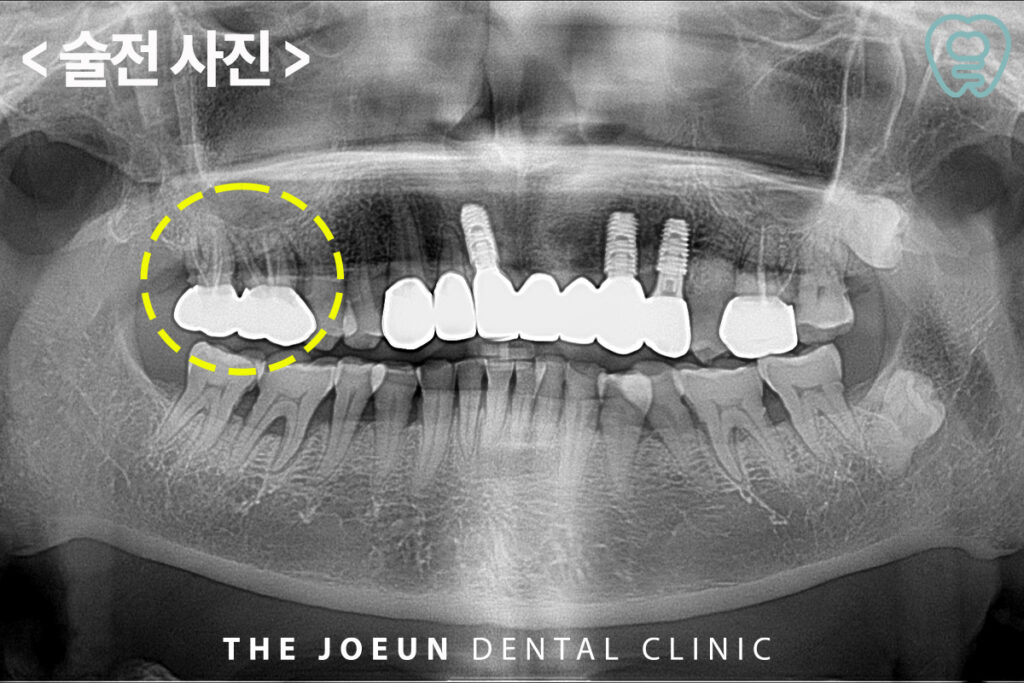

환자분께서는 오른쪽 위 씌워둔 어금니 부위에 양치를 하면 피가 나고 힘이 잘 들어가지 않는 느낌이 드신다며 내원해 주셨는데요. 파노라마를 촬영해 보니, 신경치료 후 크라운 수복이 되어 있는 오른쪽 위 어금니 부위에 염증으로 인해 잇몸뼈가 많이 녹아 있는 것을 확인할 수 있었습니다. 이미 신경치료가 되어 있는 치아라 발치가 불가피한 상황이었고, 발치 후 소실된 잇몸뼈 보강을 위해 상악동 거상술 뼈이식 및 임플란트 식립을 계획하였습니다.